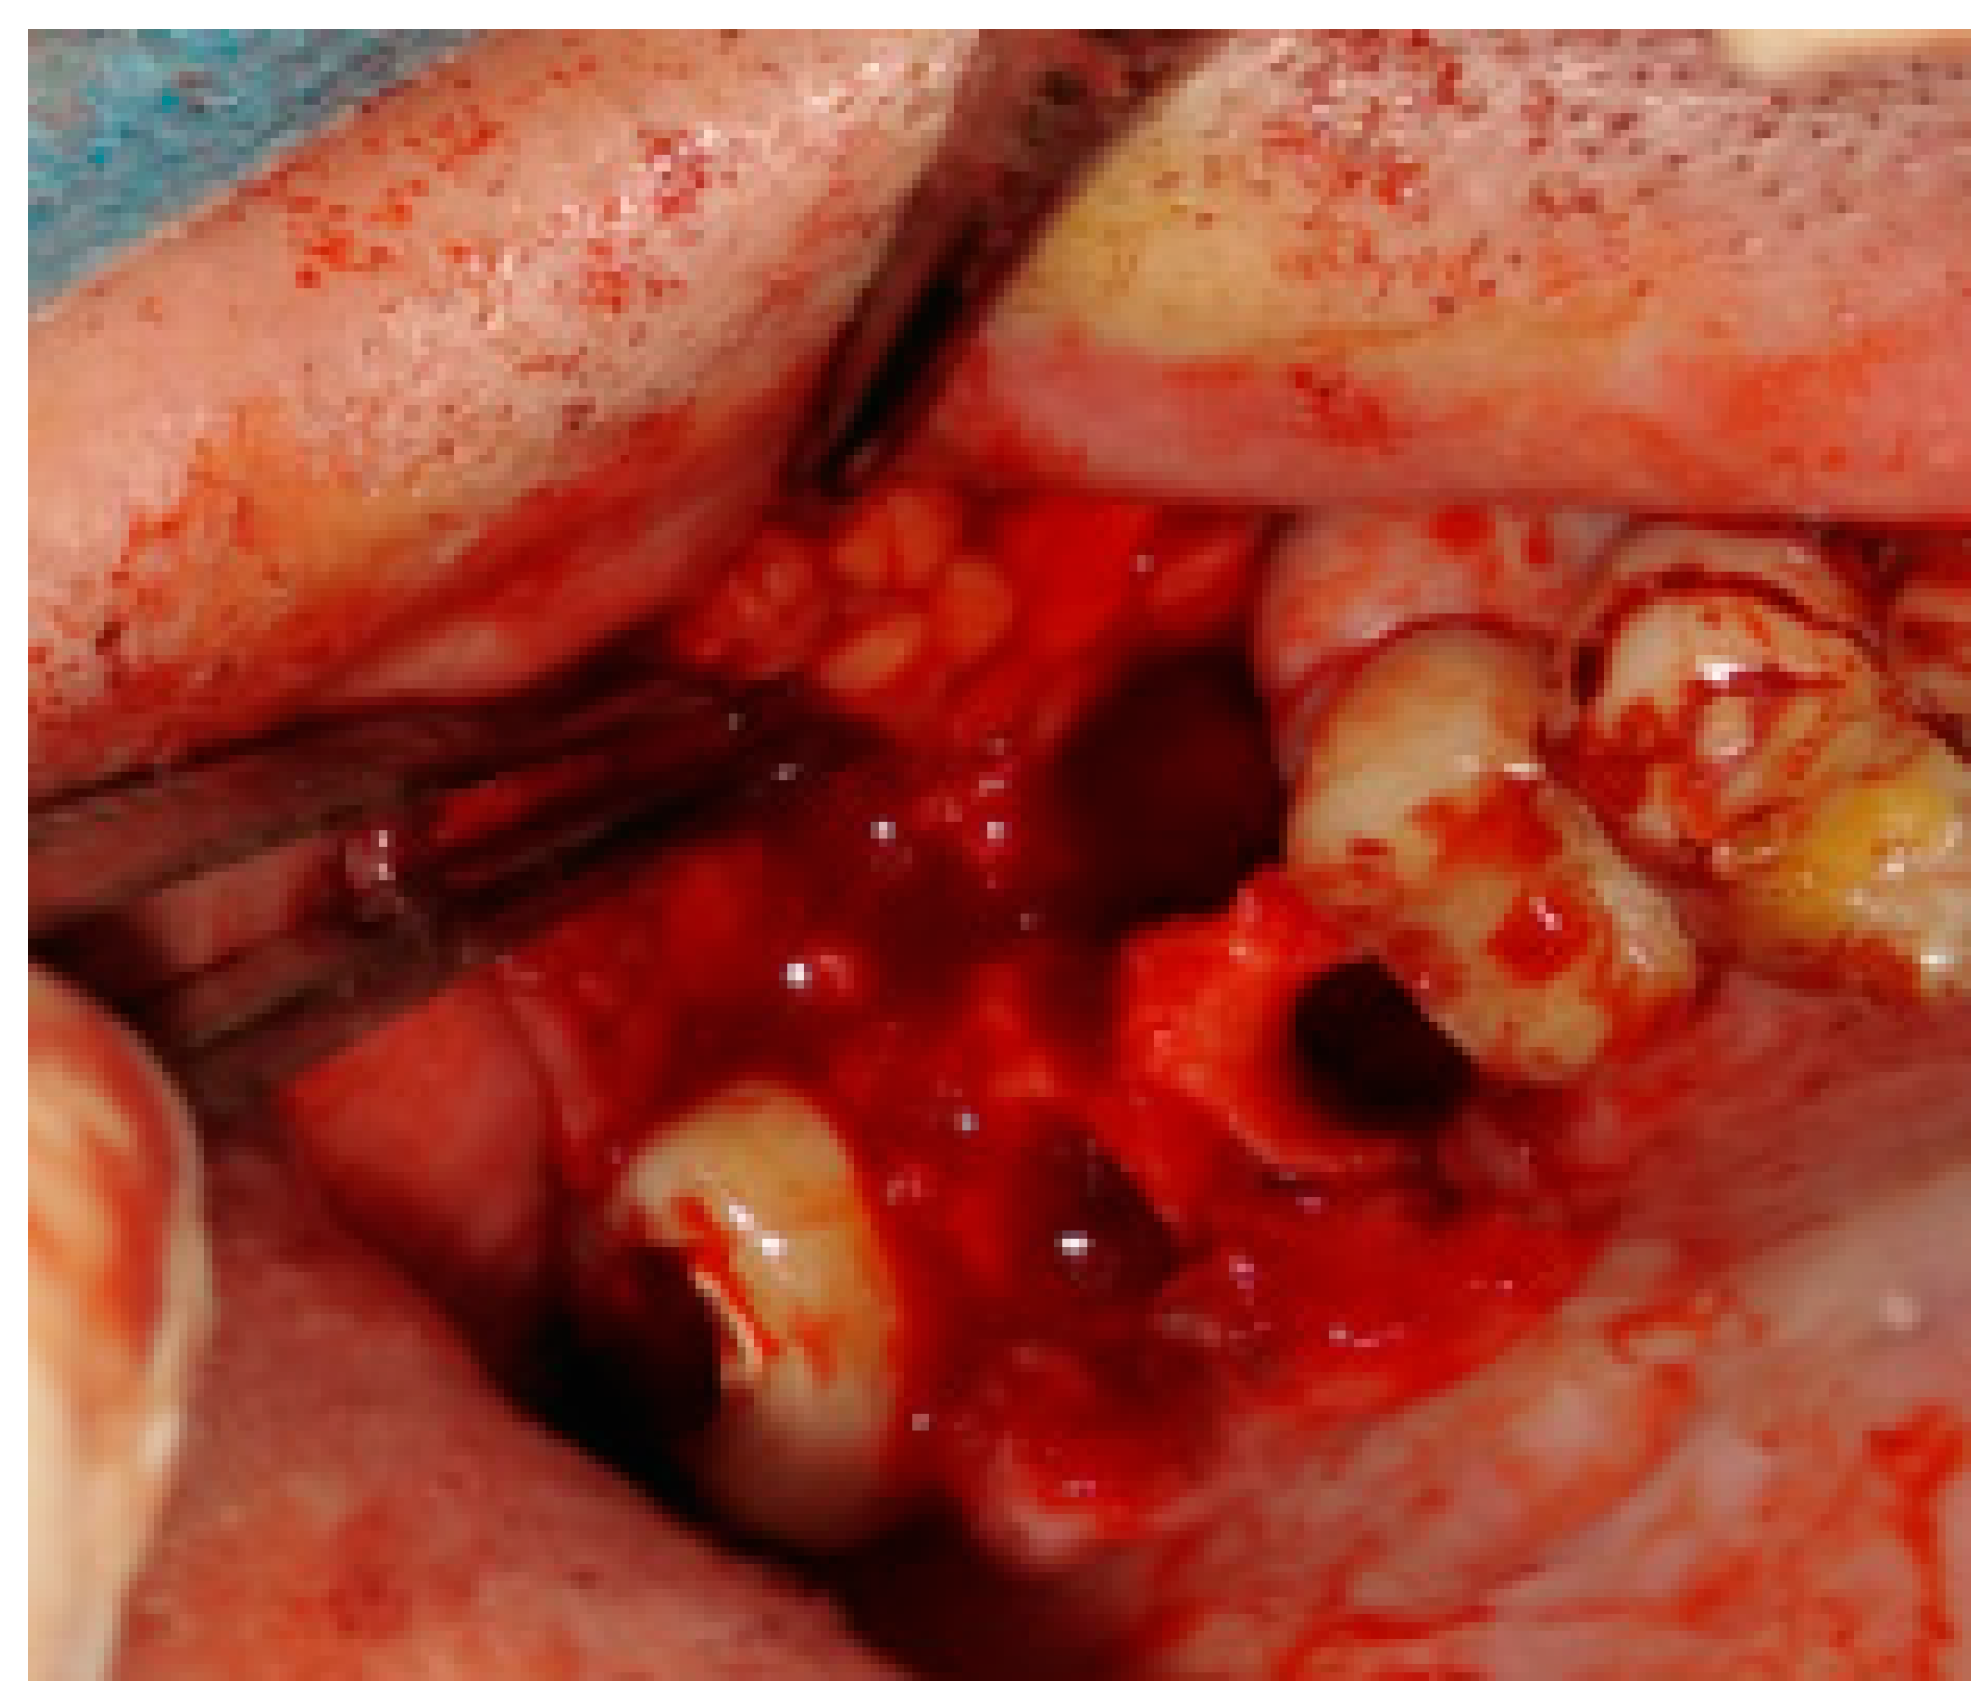

Figure 6. Bichat fat pad mobilization to cover the bone defect and close the oro-antral communication.

Figure 5. The inappropriate endodontic treatment of the upper second molar led to its inner root resorption, forming of granulation tissue, and the co-incidence of the right maxillary sinus retention cyst. The inflammation and granulation tissues, adjacent teeth, and bone were scheduled for removal. Because of combining wound debridement, cyst, and teeth removal, from the same approach, few different procedures were made. Wound debridement and removal of granulation and inflamed tissues, along with some bone, were scheduled. Because of the presence of oro-antral communication, resulting from the loss of wast bone tissue, the Bihat fat pad was used to close the communication and suture the wound in two layers. The blue, green, and red reference lines are related to CBCT evaluation in axial, sagittal, and coronal views respectively.